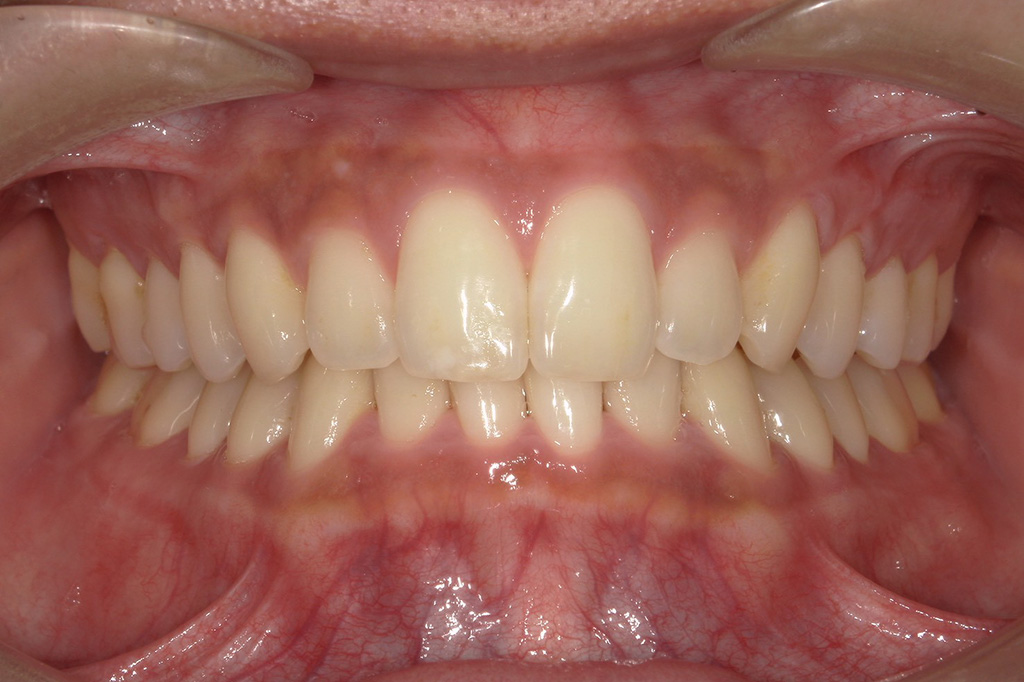

まずは初回の口腔内。

● 初回(フロス経験ゼロ)

カリエスがなく歯科医院に縁がない患者さんの、よくある口腔状態でスタートしました。